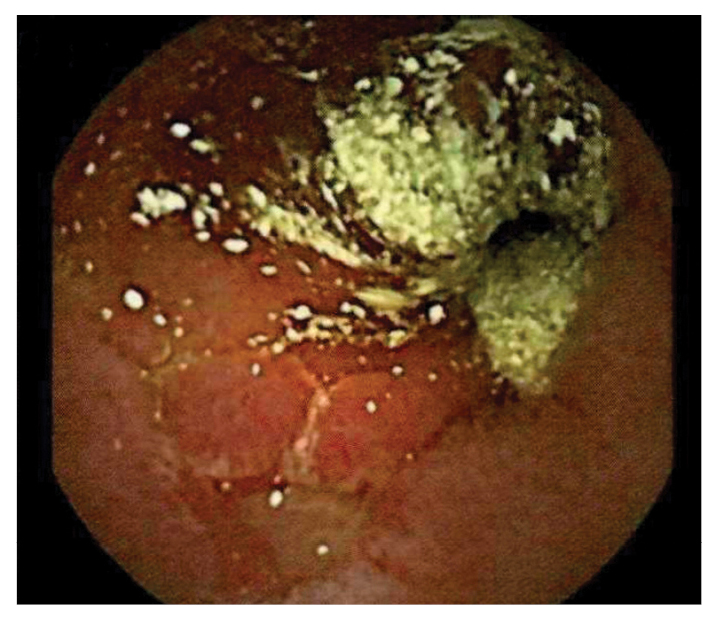

After being treated with 3 doses of pulse steroids (1 course of methylprednisolone at 1 g/day for 3 days and 2 courses at 250 mg every 6 hours for 3 days) with improvement, the patient’s abdominal pain and petechial rash recurred. Capsule endoscopy revealed ulcerations, erosions, and pus throughout the small bowel (Fig. 1), consistent with EGPA vasculitis involving the GI tract [1].

Figure 1: Capsule endoscopy showing frank pus, ulceration, and erythema of the small bowel.